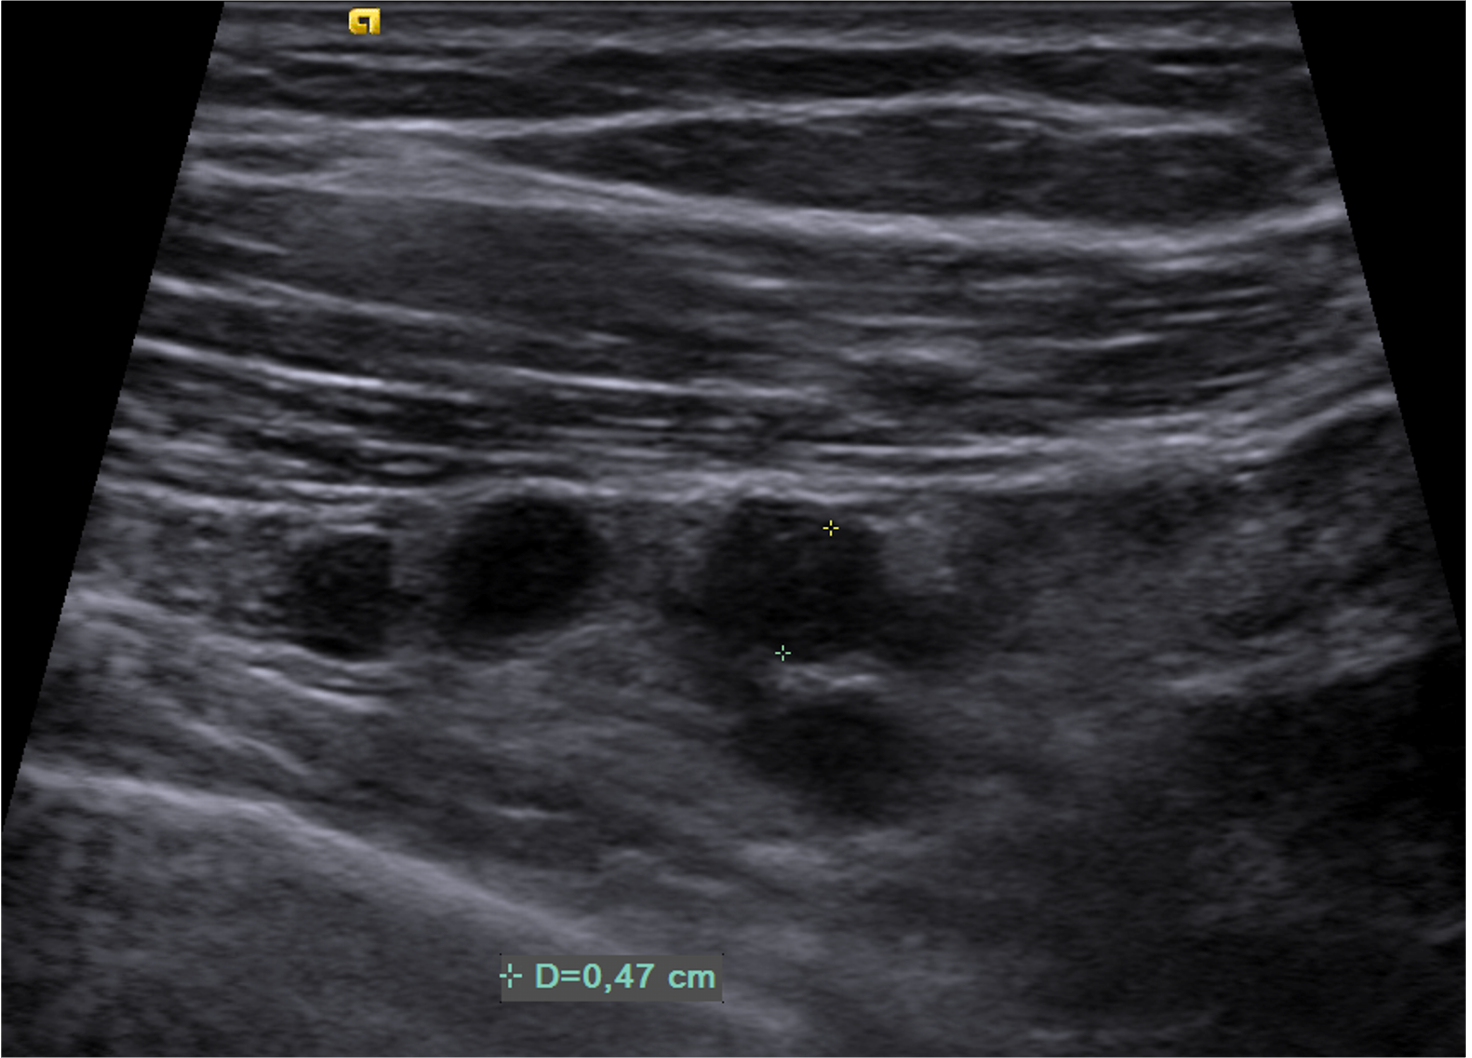

Imágenes de ecografía mamaria derecha con tranductor lineal (A, B, C), y a nivel subclavio derecho (D) y en región axilar derecha (E).

K. Región axila derecha con presencia de múltiples ganglios de morfología ovoidea, con pérdida de su hilio graso central y eje corto de hasta 6 mm. Región axilar izquierda con ganglio que conserva morfología, hilio graso con eje corto de hasta 13 mm.